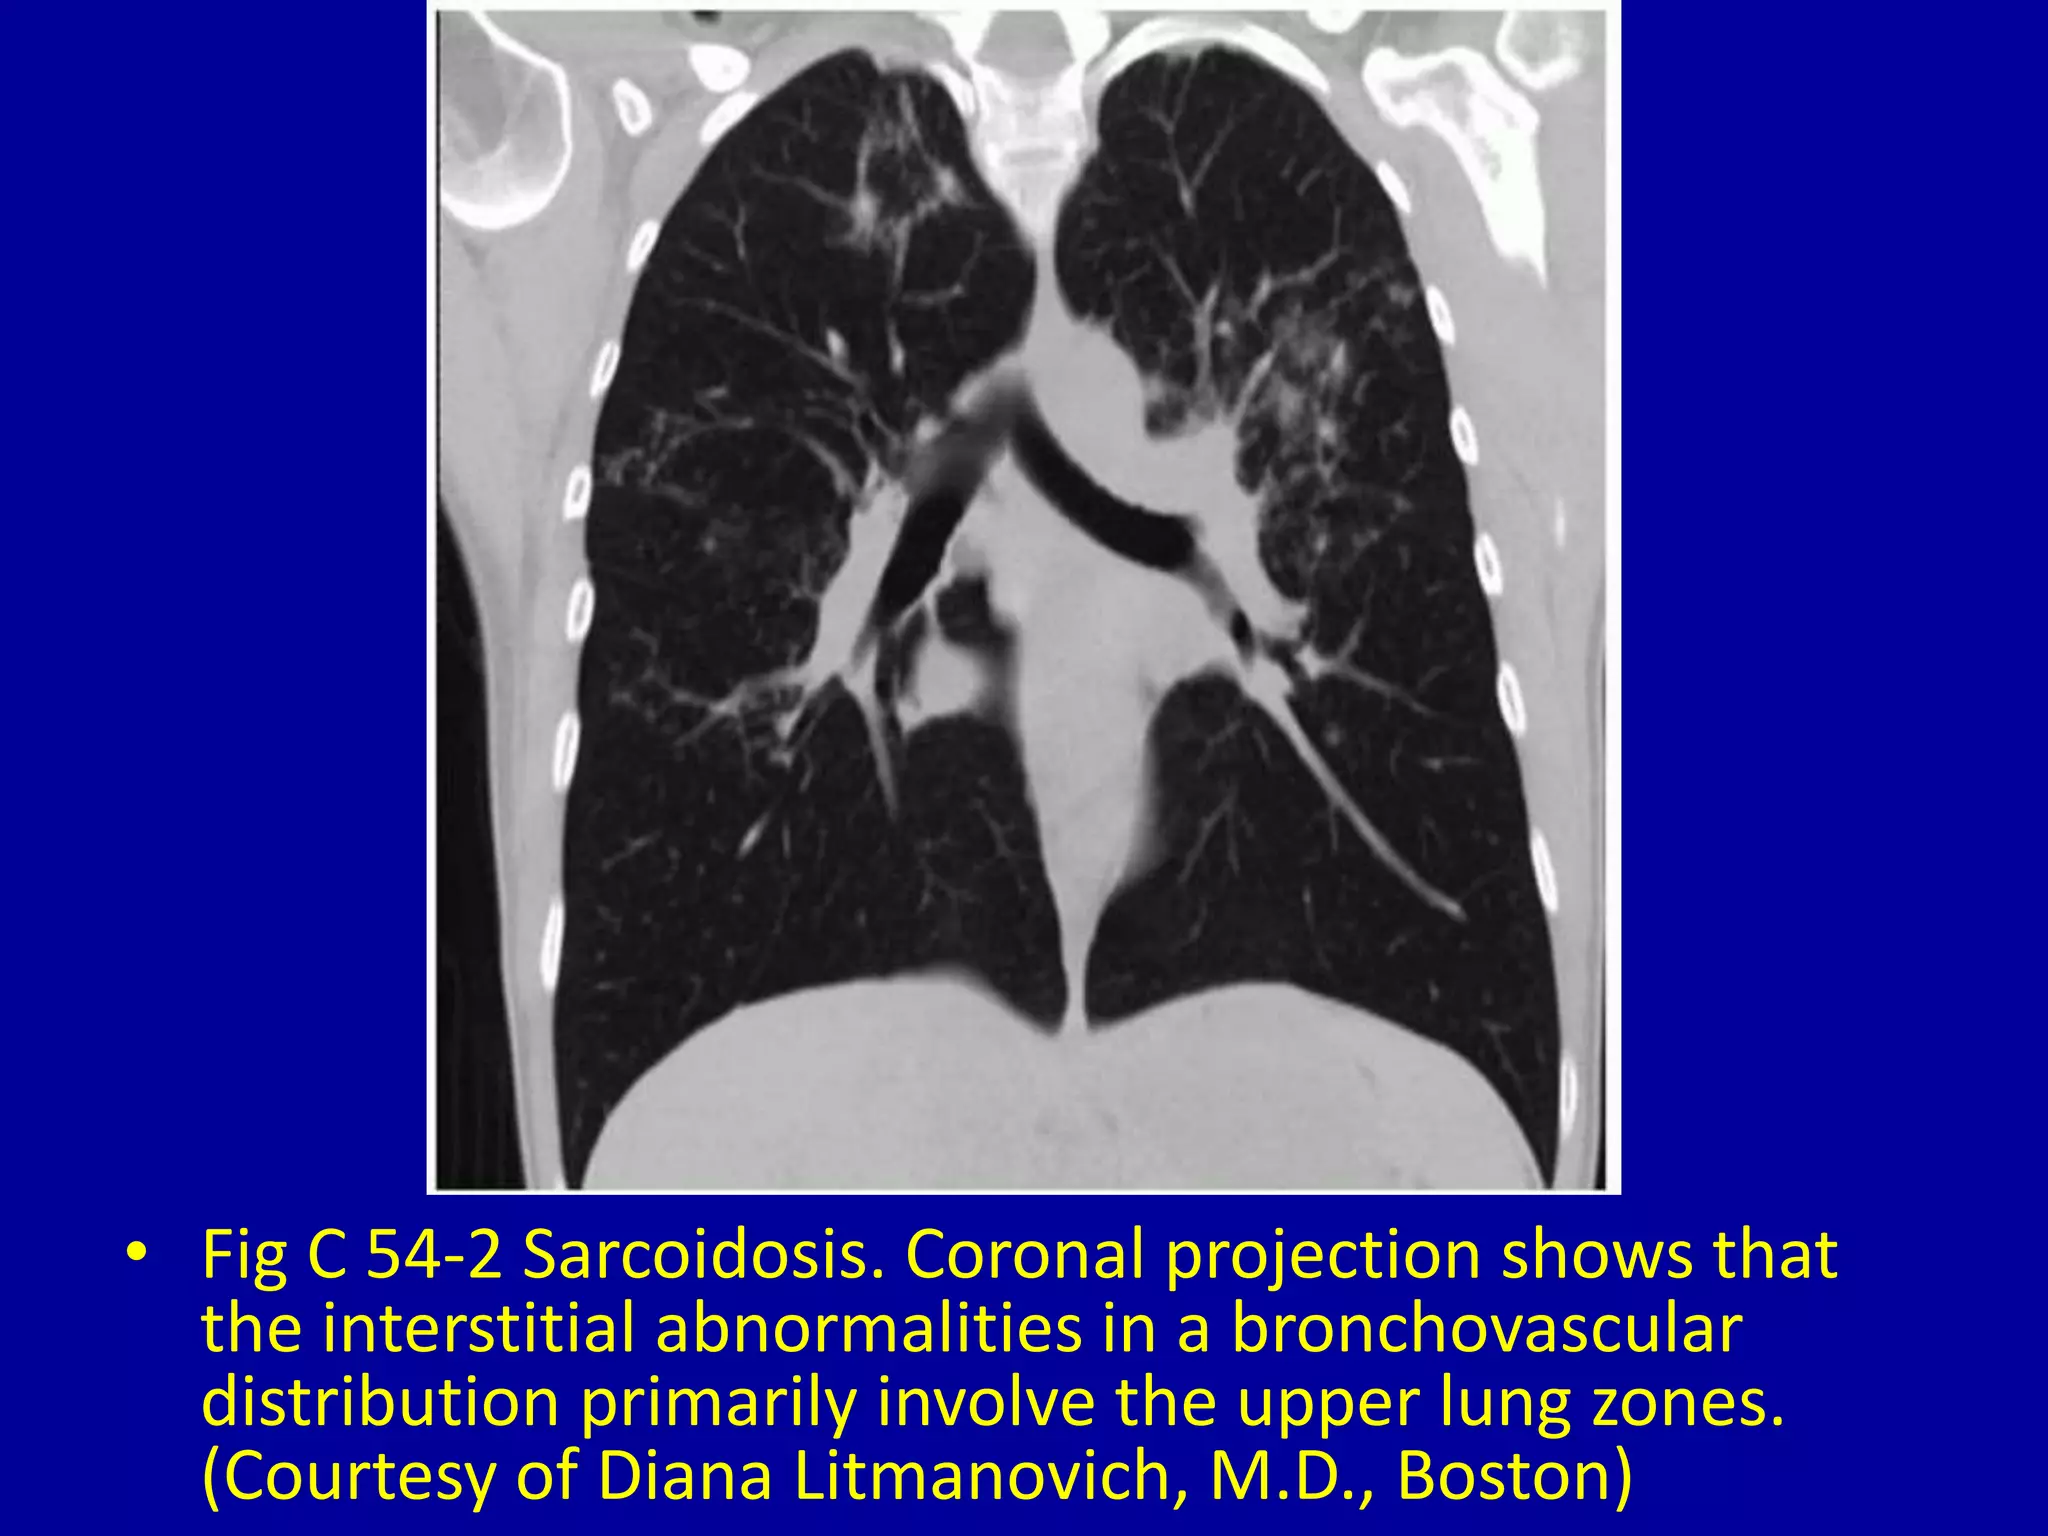

This document discusses various pulmonary diseases that predominantly affect the upper zones of the lungs. It includes 10 figures showing CT scan findings of different conditions like postprimary tuberculosis, sarcoidosis, pulmonary Langerhans cell histiocytosis, silicosis, centrilobular emphysema, chronic eosinophilic pneumonia, cystic fibrosis, allergic bronchopulmonary aspergillosis, neurogenic pulmonary edema, and ankylosing spondylitis. The images demonstrate lesions, nodules, consolidations, cysts, and other abnormalities that are largely limited to the upper lobes and regions of the lungs.